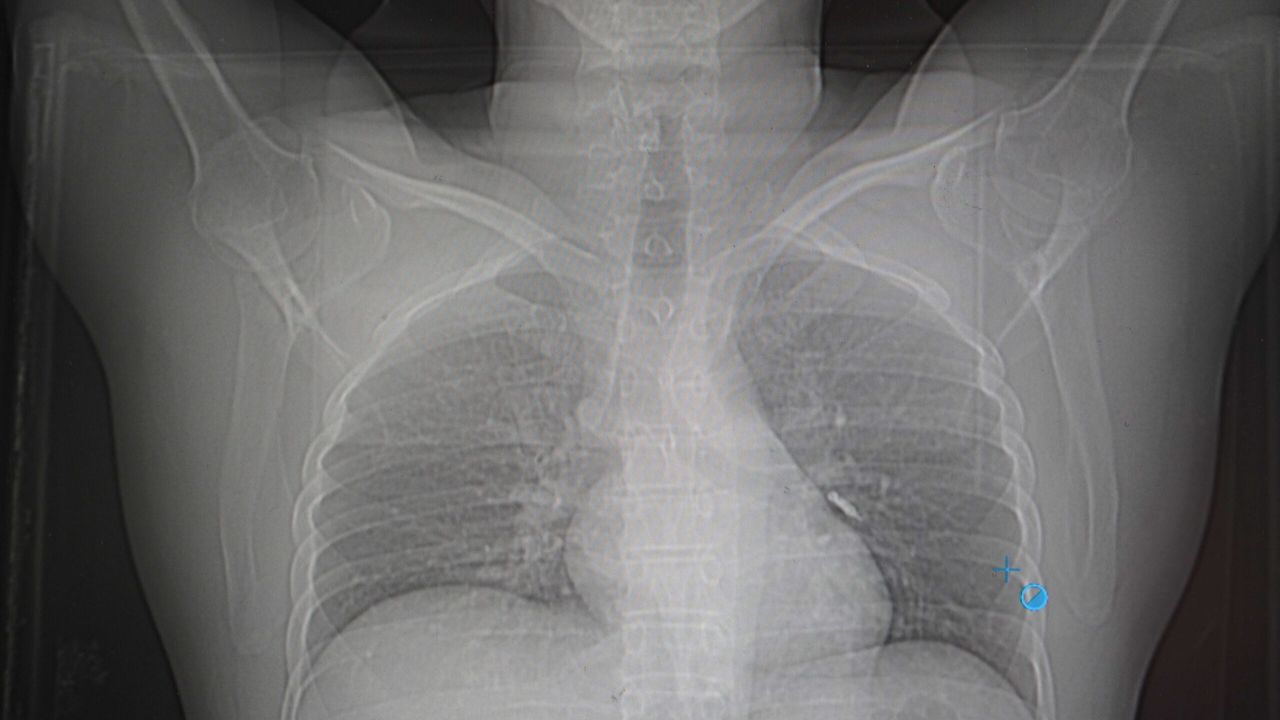

Göğüs Cerrahisi uzmanları Op. Dr. Sadullah Aksoy ve Op. Dr. Beniz İrem Ersoy Şığva’nın müdahalesiyle hastaya acil bronkoskopi uygulandı. Yapılan görüntülemede, implant vidasının sol akciğerin üst lobundaki bronşlardan birine saplandığı tespit edildi. Vidanın özel yapısı ve bulunduğu bölge nedeniyle çıkarılması oldukça güçleşti.

“Hasta bize ulaştığında genel durumu iyiydi, ancak solunum yollarından birinde tıkanıklık söz konusuydu. Bronkoskopi sırasında, vida parçasının akciğerin dar bir bronşuna saplandığını gördük. Taş kırma cihazlarına benzer bir teknikle müdahale ettik. İlk denemede çıkaramadık ama yerinden oynatabildik.”

Müdahalenin ardından yeniden bronkoskopi planlandığı sırada hasta şiddetli bir öksürük geçirdi. Yapılan kontrollerde, implant vidasının akciğerden çıkıp mideye geçtiği belirlendi. Vida daha sonra doğal yollarla vücuttan atıldı.